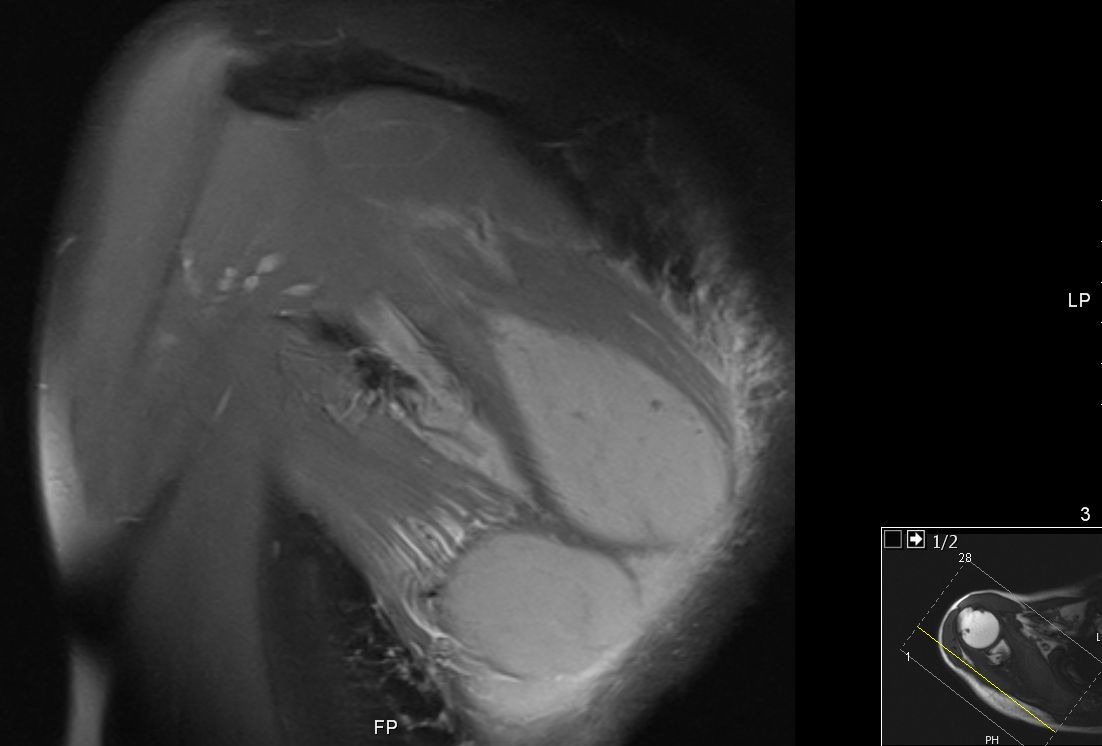

63-jähriger Mann, der vor 5 Jahren eine T - Promyelozyten - Leukämie hatte. Nach ASCT bisher rezidivfrei. Jetzt beschwerden in der rechten Schulter. Das MRT zeigt intramuskuläre Raumforderungen. Die Biopsie ergab Infiltrate der APL.